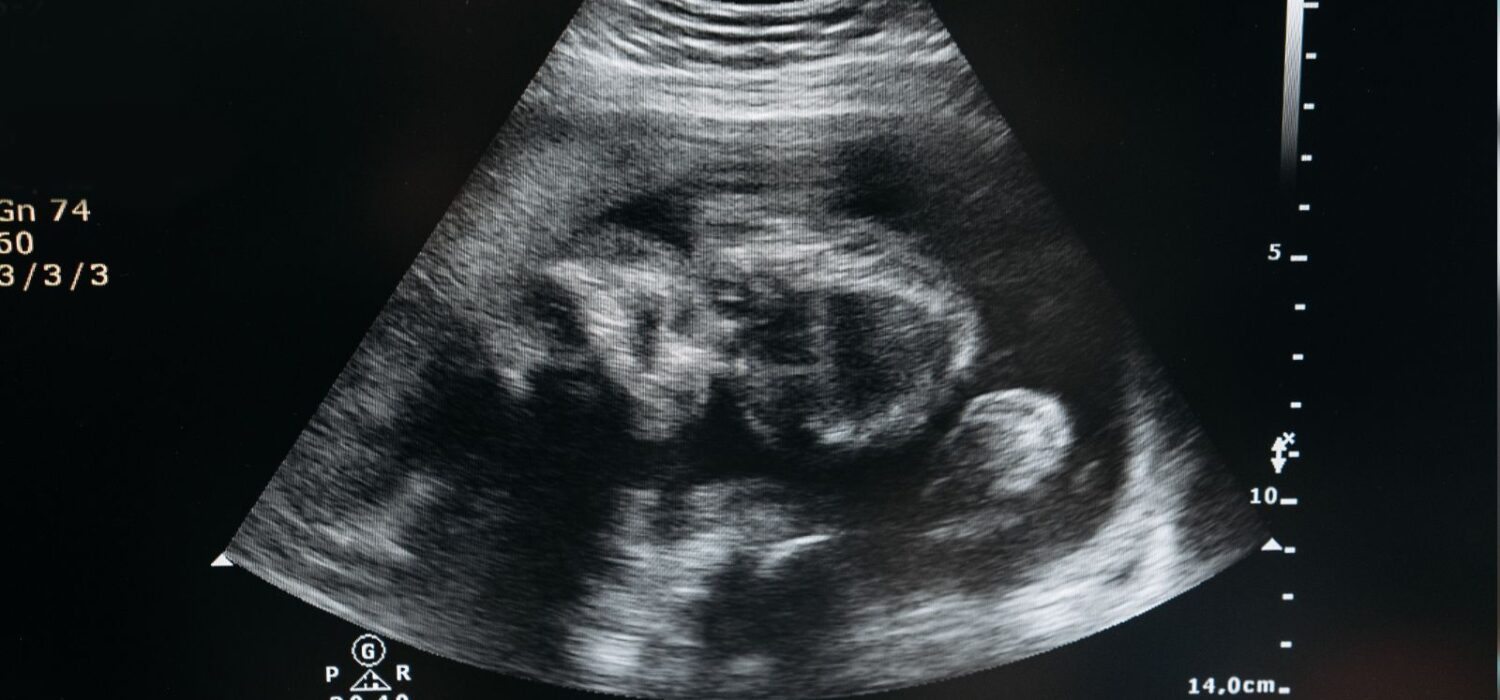

El diagnóstico se realiza mediante ecografías que muestran dos sacos gestacionales con embriones de diferentes tamaños y edades. También se pueden realizar análisis hormonales para confirmar la ovulación durante el embarazo.